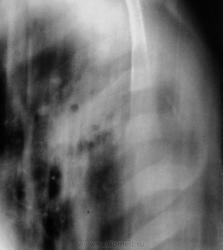

Через пол года после выписки из облтуббольницы.

Через год плановое исследование.

Через 8 месяцев пациент "простыл" и был направлен терапевтом на "флюшку" по поводу пневмонии, почему, именно, на флюорографию, ибо, состоит на учете у фтизиатра, совсем не понятно.

Коллеги, вместе с фтизиатром решили пролечить пневмонию в условиях отделения общего профиля.

Лечили интенсивно две недели. Итог лечения ниже.

Пацент направлен в облтуббольницу.